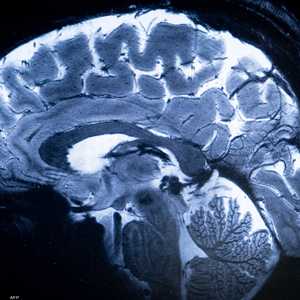

النوم ليس مجرد راحة للجسم، بل هو فترة حيوية لإعادة التوازن الداخلي، تشمل إزالة السموم، إصلاح الأنسجة، وتعزيز الجهاز المناعي.

أثناء النوم، ينخفض ضغط الدم تدريجيا في ظاهرة تُعرف باسم "الهبوط الليلي"، وهي ضرورية لحماية القلب والأوعية الدموية.

عند عدم الحصول على نوم كاف أو متقطع، يتعطل هذا الهبوط الليلي، ويزداد الضغط على القلب، مما يرفع خطر الإصابة بارتفاع ضغط الدم، والنوبات القلبية، والسكتات الدماغية على المدى الطويل.